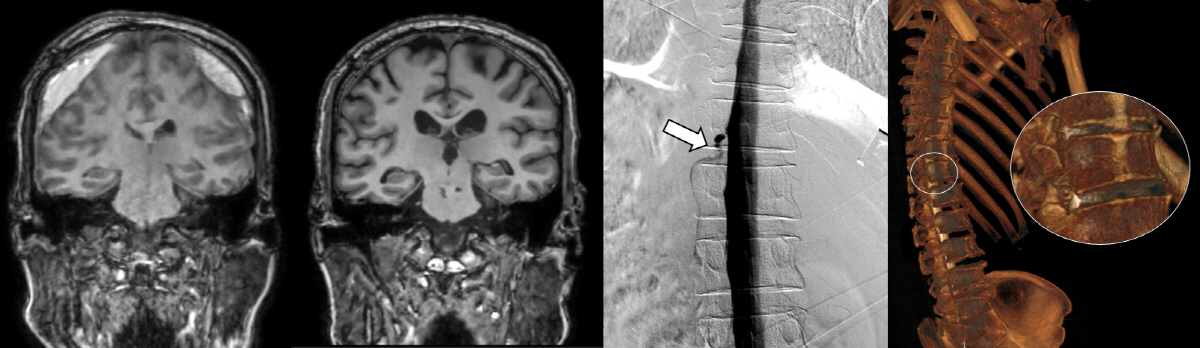

일반적인 자발성 두개내 저압증과는 달리, 그 아형인 뇌척수액 정맥 누공은 MRI에서는 정상 소견을 보일 수 있어 원인 규명부터 치료까지 난항을 겪는 질환이다.

실제로 이번에 치료를 받은 뇌척수액 정맥 누공이 있던 환자 4명 모두는 세브란스병원에 오기 전 뇌압이 낮아져 두통이 생기는 '자발성 두개내 저하증'이 의심됐으나, 척추 MRI와 단순 척수 조영술 검사에서는 전부 정상 소견을 보였다.

세브란스병원은 최근 DSM을 국내 최초로 도입해 이와 같은 기존 진단법의 한계를 극복했다. DSM(Digital Subtraction Myelography, 디지털 감산 척수조영술)은 척수에 조영제를 주입하고 모니터 화면으로 뇌척수액의 흐름을 실시간으로 확인할 수 있다. 이를 통해 뇌척수액이 새나가는 구멍을 정확하게 찾아낼 수 있게 됐다.

DSM과 더불어 세브란스병원이 함께 진행 중인 측위 CT 척수 조영술까지, 모두 뇌척수액 정맥 누공을 진단할 수 있는 최신 기법이다.

이번에 세브란스병원을 찾은 환자들은 DSM 검사와 측위 CT 척수 조영술로 뇌척수가 새어나가는 부위를 정확히 진단·치료받고, 뇌압을 회복했으며 경막하출혈도 사라졌다. 이에 따라 환자들이 보였던 인지기능 저하와 보행장애도 모두 호전됐다.

하우석 교수는 "자발성 두개내압 저하증과 특별한 외상이 없이 발생하는 경막하출혈의 원인 중 하나였던 뇌척수액 척수 누공은 두통, 인지능력 저하 등 심각한 고통을 일으키지만, 기존 진단법으로는 원인 규명이 쉽지 않던 상황"이라며 "세브란스병원이 도입한 DSM과 측위 CT 척수 조영술로는 척수액 누출이 발생하는 지점을 정확히 찾아내 치료할 수 있다"고 말했다.